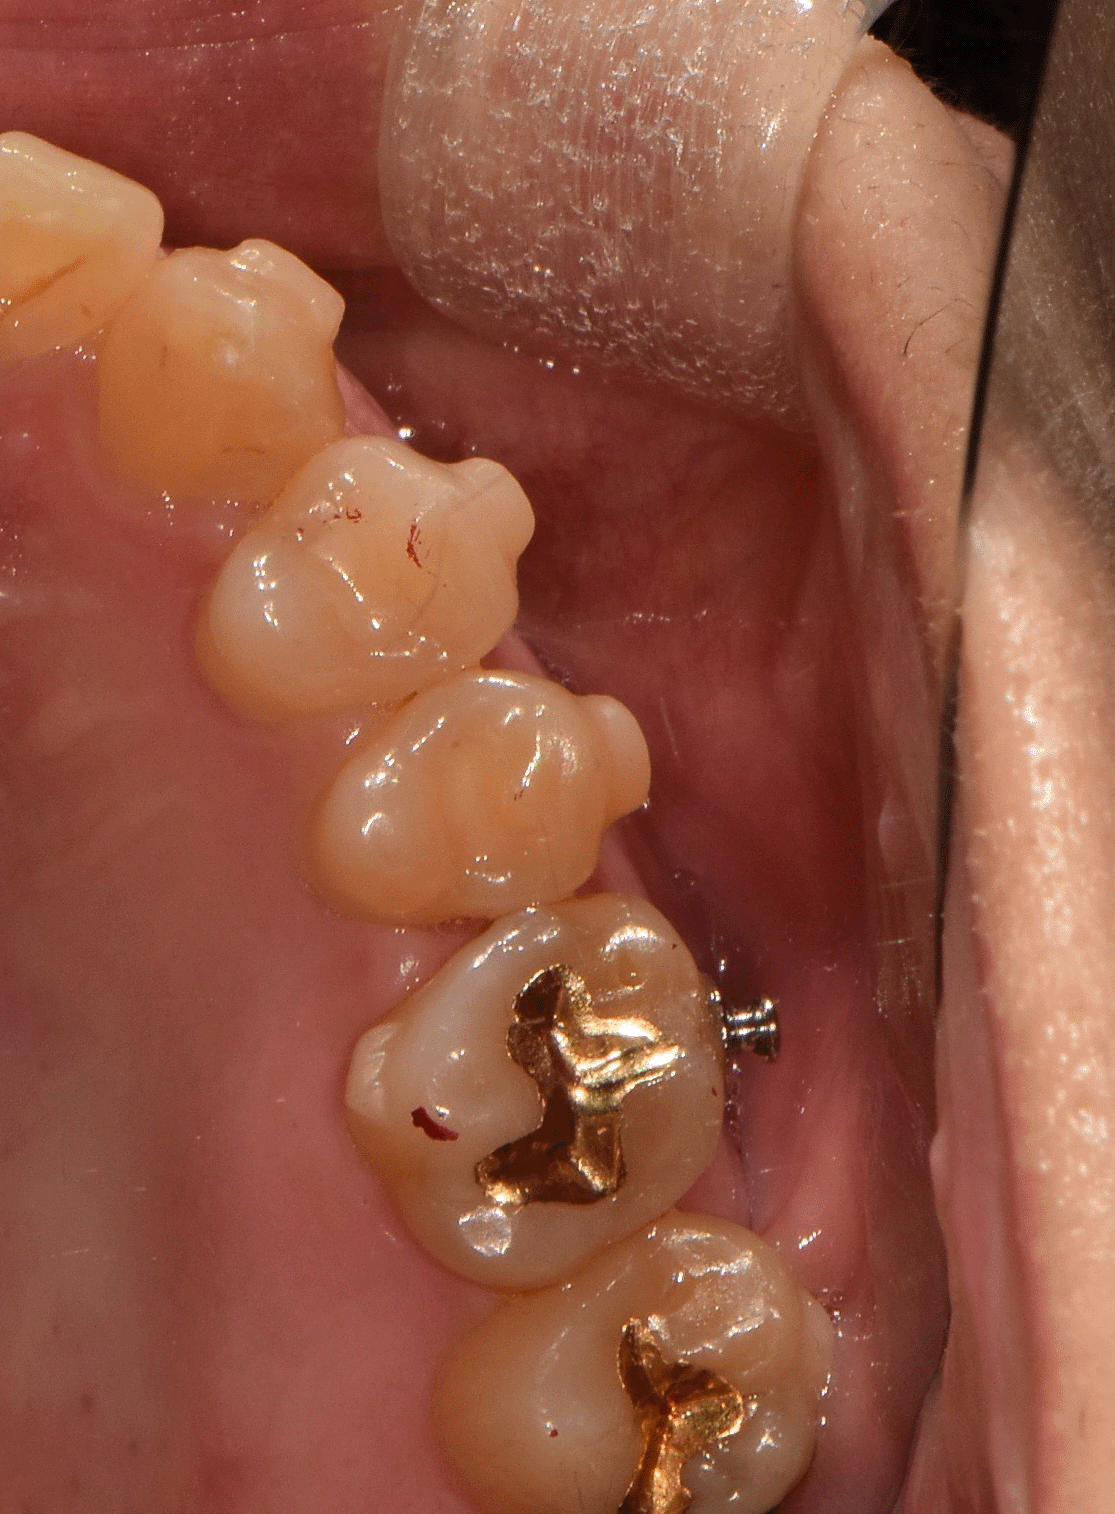

또한 힘을 많이 받는 어금니에는

“버튼(button)”을 붙여서

고무줄의 힘을 더욱 용이하게

도와주는 보조 장치도 달아드렸습니다.

추가로 양측 아래 어금니에

금 인레이를 해두신 치아는

기존 보철물 하방으로

2차 우식이 생겨서 제거했습니다.

제거하는 과정에서

충치의 깊이가 깊고 크기가 커서

보철물의 유지력과 지지력을 위해

치아색이 나는 지르코니아 크라운으로 진행했습니다.